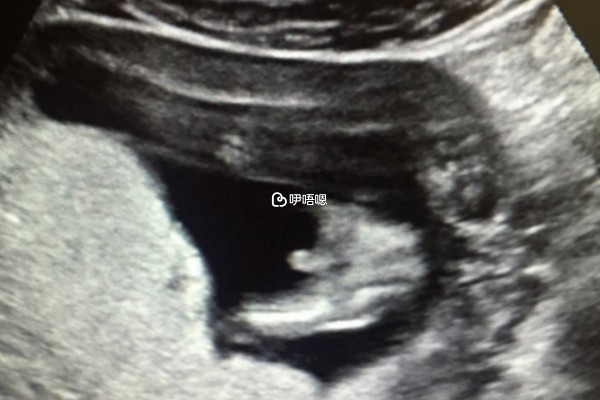

試管嬰兒移植後停育的胚胎男女都有,佔比是差不多的,這與寶寶是男孩還是女孩並沒有任何關係,無論孕婦懷的是男孩子還是女孩子,在胚胎髮育過程中都會面臨胎停育的可能,造成胎停育的原因有很多,例如孕卵異常、胚胎髮育緩慢、母兒的血型不合、胎盤發育不良等等,唯獨和胎兒的性別沒有關係。

發生胎停育可能是母體因素或男方因素,如果女性體質差,或者患有疾病,比如宮頸閉鎖不全、黃體功能不全、子宮內膜異位症、免疫因素、糖尿病、甲亢等,發生胎停育的機率會更大。如果男性精液中有大量細菌生長、精子畸形率高等問題,也有可能導致胎停育。

因為我們國家是不允許透露胎兒性別的,但人們還是希望可以有個兒子,所以發生胎停後,會下意識的覺得是個男孩子,久而久之就有了發生胎停育的多數是兒子的說法,但其實是沒有科學依據的。一旦發生胚胎停止發育後,需要及時到醫院檢查和治療,調理好身體才能更好的生育。